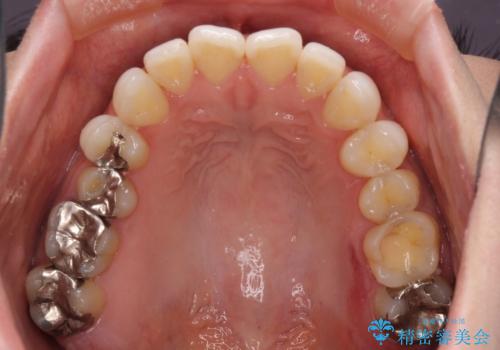

前歯のデコボコをすっきりと インビザライン矯正

- 前歯のデコボコを治したいとのことで来院された患者様です。

下顎が前方位にある方であったため、下顎の歯列全体の後方移動とIPR(歯と歯の間を削る)によってデコボコが解消するように設計し、インビザラインにより治療を行うこととしました。